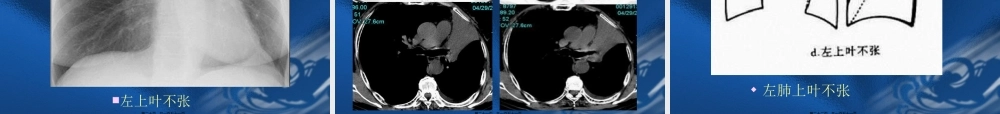

呼吸系统根本病变的影像学表现第一页,共一百五十一页。第一节支气管阻塞性改变第二节肺部改变第三节肺门的改变第四节胸膜病变第五节纵隔的改变第六节膈的改变第二页,共一百五十一页。第一节支气管阻塞性改变原因:腔内性:肿瘤、异物、炎症、结核、先天性狭窄。腔外性:淋巴结增大压迫。后果:局部阻塞:阻塞型肺气肿。完全阻塞:阻塞型肺不张。第三页,共一百五十一页。第一节支气管阻塞性改变一、阻塞型肺气肿(obstructiveemphysema)1、两肺阻塞性肺气肿:见于慢支及支气管哮喘。影像表现:肺野透过度增加,与呼吸时相关系不大;肺纹理稀疏变细,可见肺大泡。横膈低平,活动度减低;胸廓呈桶状,肋间隙增宽;心影狭长呈垂位心型,心后间隙增宽。第四页,共一百五十一页。第一节支气管阻塞性改变2、局限性阻塞性肺气肿一侧性肺气肿:一叶性肺气肿:影像表现:肺内表现同上;纵隔向健侧移位或移位不明显。气管内异物可表现为纵隔摆动。支气管断层或造影有利于诊断。第五页,共一百五十一页。第六页,共一百五十一页。第七页,共一百五十一页。正常肺组织病理图肺泡肺泡壁终末细支气管第八页,共一百五十一页。肺气肿:终末细支气管远侧气腔持久性异常增大,伴受累气腔壁的破坏小叶中央型:两肺弥漫分布,直径小于1cm,无明显的壁,其内见小点状中央细支气管动脉。全小叶型:两肺弥漫分布圆形类圆形的无壁低密度区间隔旁型:位于胸膜下〔肋胸膜、膈胸膜及纵隔胸膜〕呈带状分布的不规那么空气密度第九页,共一百五十一页。次级肺小叶:肺小叶,最小的肺组织单位,小叶细支气管和小叶动脉,约1-2.5cm大小,分出3-5支终末细支气管终末细支气管以远的肺结构为腺泡,约4-7mm小叶中心型肺气肿全小叶型肺气肿第十页,共一百五十一页。小叶中央型全小叶型间隔旁型第十一页,共一百五十一页。肺纹理减少、横膈变平、桶状胸、心影狭长。第十二页,共一百五十一页。阻塞性细支气管炎(BronchiolitisObliterans)指细支气管发炎的病变,导致支气管壁纤维化以及管腔阻塞。第十三页,共一百五十一页。阻塞性细支气管炎(BronchiolitisObliterans)呈现—马赛克灌注,磨玻璃密度区肺血管增粗。支扩肺血管增粗第十四页,共一百五十一页。第一节支气管阻塞性改变二、阻塞性肺不张〔obstructiveatelectasis〕1、一侧性肺不张:一侧主支气管完全性阻塞的后果。影像表现:患侧肺野均匀一...